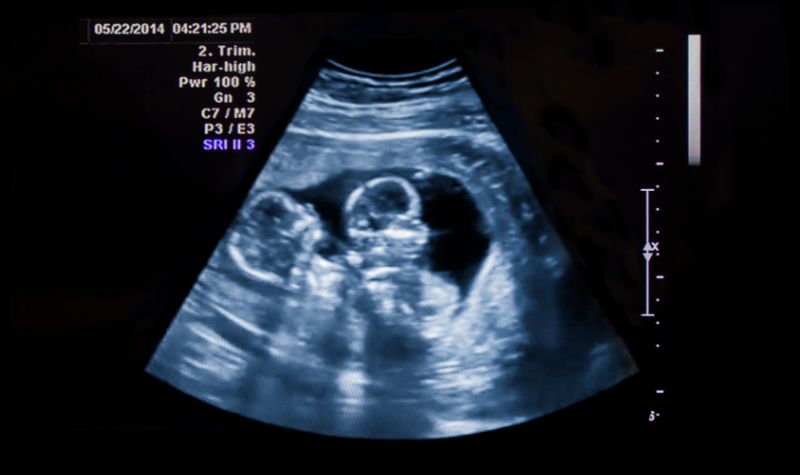

Terkadang pada saat awal kehamilan tidak bisa dipastikan apakah seorang ibu hamil sedang mengandung bayi kembar atau tidak. Sampai terjadinya USG pada tri semester pertama, mengutip dari Healtydigest.com, Selasa (25/10/2022).